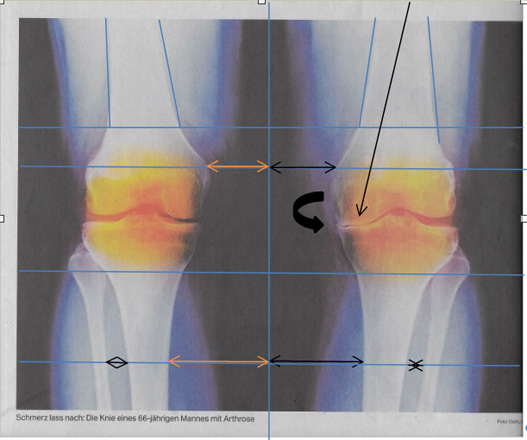

Oberkörper seitliche Ausweichhaltung führt über die Hebelwirkung zu Überbelastung der Knie-Innenseite (Folge Arthrose wird festgestellt?)

Dieses Beispiel: Abgenutzter Knorpel Ursache: Seitliche Oberkörper Ausweichhaltung |

Befindet sich Spannung und Gegenspannung nicht im Gleichgewicht, verzieht es das Skelett. Dadurch verändern sich Knochen- und Gelenkstellungen, was zu einseitiger Überbelastung führt und vielmals als Arthrose betrachtet wird.

Wie kann die Fehlstatik aus Körperteil-Aufnahmen Ursachen bezogen erkannt werden, die zu Knochen-, Gelenk-, Wirbelkörper-, Bandscheiben-Veränderungen führen?

Anhand einiger Röntgen / MRI Bilder etc. Zeigen wir dies auf. Bilder Getty / Getty Image

Was kann eine Skelett-Bildaufnahme betreffend die Arthrose aufzeigen?

Wie können so die Fehlstellungen Ursachen bezogen aufgezeigt und behandelt werden?

Körperaufnahmen in Schonhaltung werden Beschwerden sichtbar gemacht, ohne deren Ursachen zu berücksichtigen. Trotz optimaler Bildqualität und hochauflösender Aufnahmen werden die Ursachen der Beschwerden so nicht besser sichtbar, weil eine veränderte Muskelspannung auch eine veränderte Aufnahme zur Folge hat.

So entstehen Beschwerdebilder, bei denen Veränderungen sichtbar werden, ohne den Grund dafür aufzuzeigen.

Dies wiederum führt zu Punktuellen Überbelastungen und wird dann als Abnutzungen, Ablagerungen an Gelenken und Wirbelkörper führen. Was dann z.B. als Arthrose oder Bandscheibenvorfall bebildert wird.

Statt des Beckenausgleiches werden Rückenschmerzen, Hüftbeschwerden und Fehl-Stellungen der Beine und Füsse am Ende einer Fehlbelastungskette behandelt. Die Verspannungslinien führen zu einseitigen Gelenküberbelastungen und werden dann als Arthrose beschrieben und bebildert.